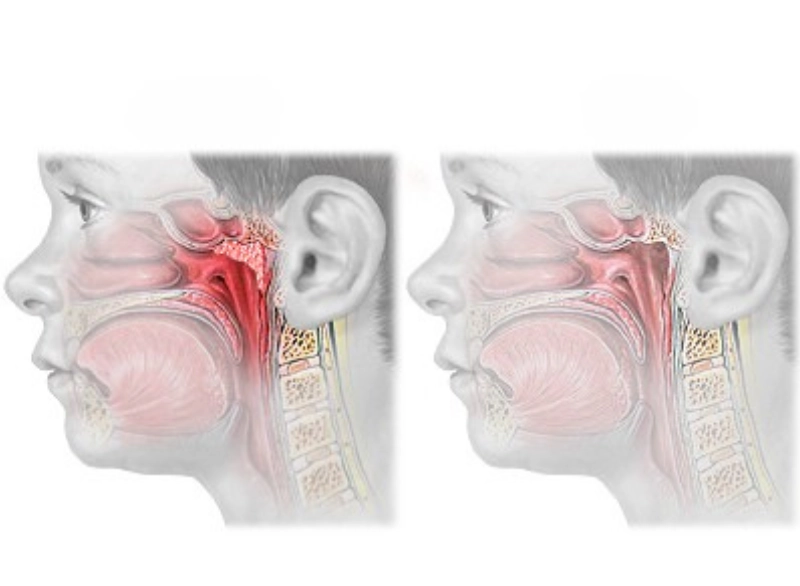

Adenoidectomy is the surgical removal of the adenoids—small lymphatic tissue located behind the nasal passage. When these become enlarged or infected frequently, they can block airways, cause snoring, breathing problems, and persistent ear or sinus infections.

Under general anesthesia, the adenoids are removed through the mouth—no cuts on the outside. The procedure takes less than an hour.